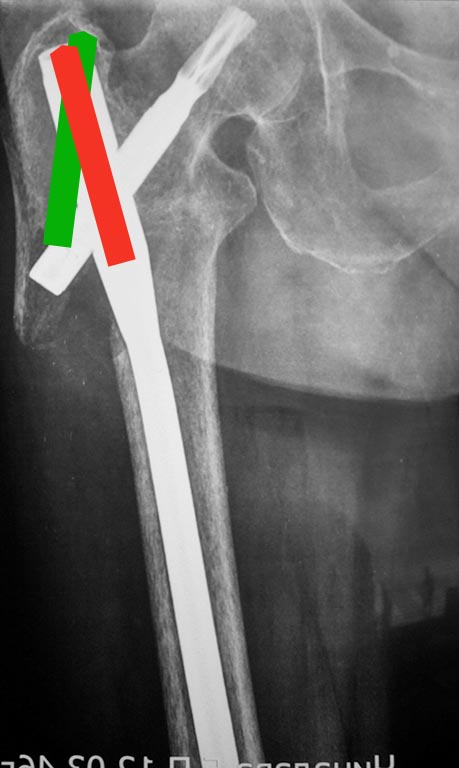

Ни угол в гвозде, ни мнимое или реальное отсутствие латеральной стенки здесь ни при чем. Проблема обусловлена латеральной точкой введения и медиальным направлением в центральном отломке. На приложенной картинке зеленым обозначено должное положение.